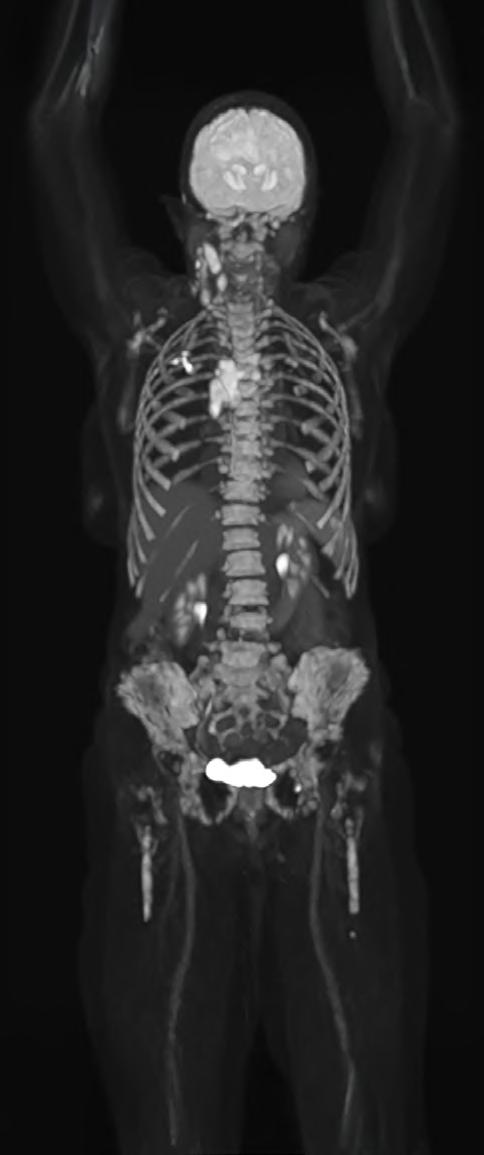

The Whole Picture: Total-Body PET and the Future of Biopharma

What if a clinical scan could transform biopharmaceutical innovation and patient care, streamlining drug development, clinical trials, and complex disease diagnosis? Total-body Positron Emission Tomography (PET) imaging is turning that vision into reality, offering a full-body, real-time view of human physiology.

Total-body PET is redefining what is possible in molecular imaging and biopharmaceutical development. This advanced PET technology can deliver full-body scans in minutes, with a sensitivity of up to 40x greater than conventional standard field PET scanners1 and potential for significantly lower radiation exposure. This opens exciting new avenues for research and discovery. It enables clinicians to study disease in real time across the whole body, revolutionising how we diagnose, stage and treat complex conditions like cancer, cardiovascular disease and neurodegenerative disorders. For patients, this means faster scans and earlier interventions, with the opportunity for more personalised treatments. For research and industry, it unlocks a powerful new platform for evaluating novel therapies, tracking their behaviour and accelerating their path to market.

Continued technological advances in hardware and software have led to a new generation of PET scanners with far greater sensitivity and resolution. While conventional PET relies on multiple bed positions and generating multiple images to acquire

a whole picture of the body, total-body PET has a field of view wide enough to take an image from head to toe in a single scan, and a detector capable of 40x higher sensitivity.¹ This means the whole body can be imaged faster, at higher resolution and in real-time. It also means lower doses of radiotracer are required to generate the same amount of detail (Table 1).1,3

Feature

Conventional PET Total-Body PET

Large Axial Field of View (LAFOV) 15–20cm >100cm*

Sensitivity Moderate Ultra-high (up to 40x higher for whole-body images)

Average Total-Body scan time** 10–30 min 30 seconds–3 minutes

Average radiation dose for a full-body scan** ~370 MBq ~9.25 MBq

Dynamic imaging potential (continuous capture of data over time)

Patient throughput

Tracers can be followed for ~3 half-lives, limiting dynamic imaging

Lower

Tracers can be followed for 5–6 additional half-lives, enabling whole-body, real-time imaging

Potential for twice as many clinical scans per day

*Scanners in the NPIP network have a LAFOV of between 106–194cm. **Based on (18F)-FDG scan procedures.

Table 1. Differences between conventional PET scanners and total-body PET scanners.1,4,5,6

Importantly, total-body PET does not replace conventional PET imaging. Conventional PET remains indispensable in clinical practice, especially when imaging needs are localised to a specific area of the body. But for complex diseases that span multiple organ systems or in cases where lower doses of radiation are required, total-body PET offers a transformative new lens:

Clinical images provided by Siemens Healthineers AG ©2025